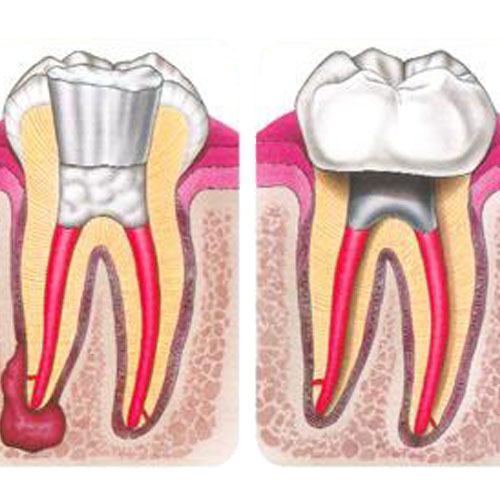

Popularmente conhecida como tratamento de canal, consiste na remoção do nervo e descontaminação das paredes internas e obturação da raiz.

Clique na imagem para ampliar: